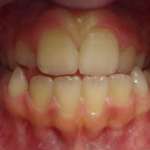

La tecnica Invisalign® nel paziente in crescita Premium

i principi di base della tecnica ortodontica digitale Invisalign nel trattamento delle malocclusioni nel bambino e nell’adolescente